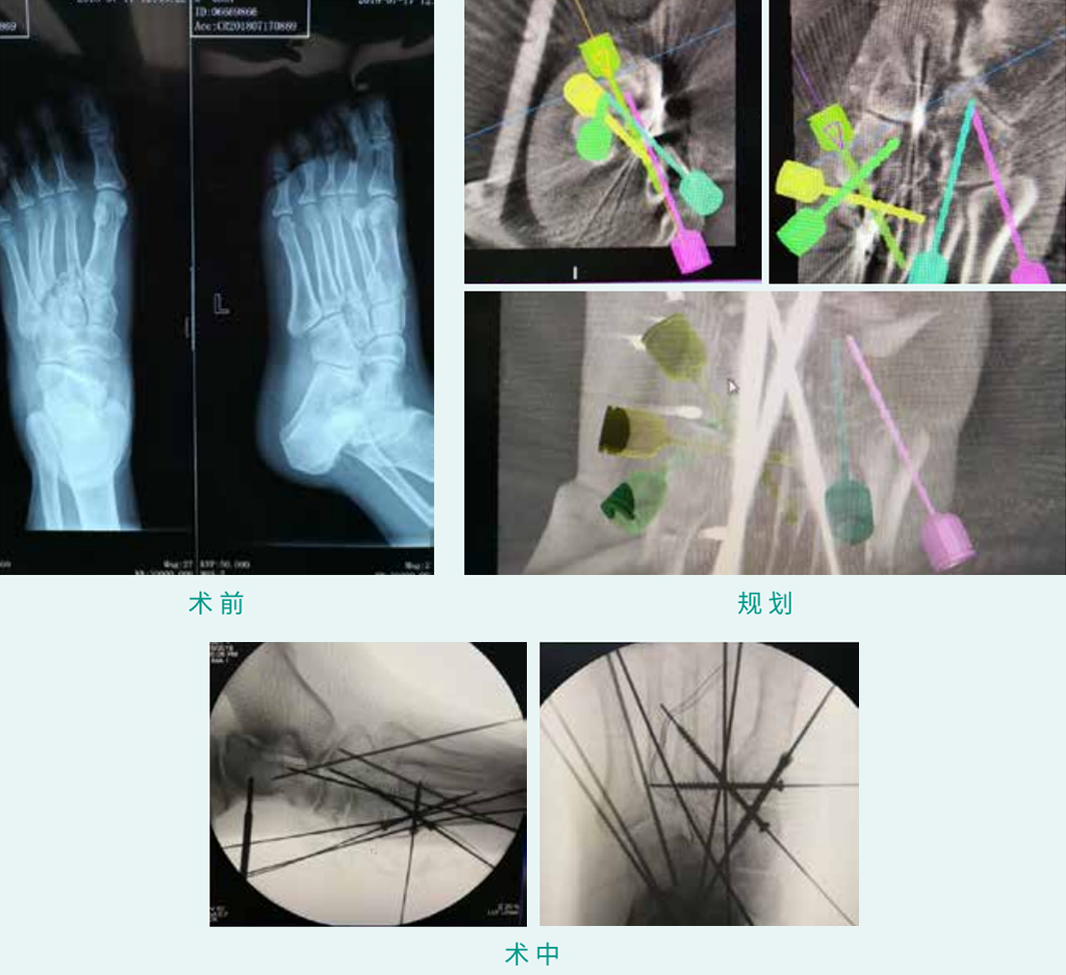

TiRobot ? Lisfranc Fracture

еӨ©зҺ‘? иҫ…еҠ©LisfrancйӘЁжҠҳз»Ҹзҡ®з©әеҝғиһәй’үеҶ…зүўйқ жңҜ

еҹәжң¬жғ…еҪўпјҡжӮЈиҖ…з”·пјҢпјҢ53еІҒпјҢпјҢи·–и·—жһўзәҪйӘЁжҠҳи„ұдҪҚ

жңәжў°дәәзҙҜз§Ҝз”Ёж—¶пјҡ30еҲҶй’ҹ

жӨҚе…Ҙзү©пјҡ5жһҡз©әеҝғиһәй’ү

з—…дҫӢжіүжәҗпјҡеҢ—дә¬з§Ҝж°ҙжҪӯеҢ»йҷў жӯҰеӢҮ